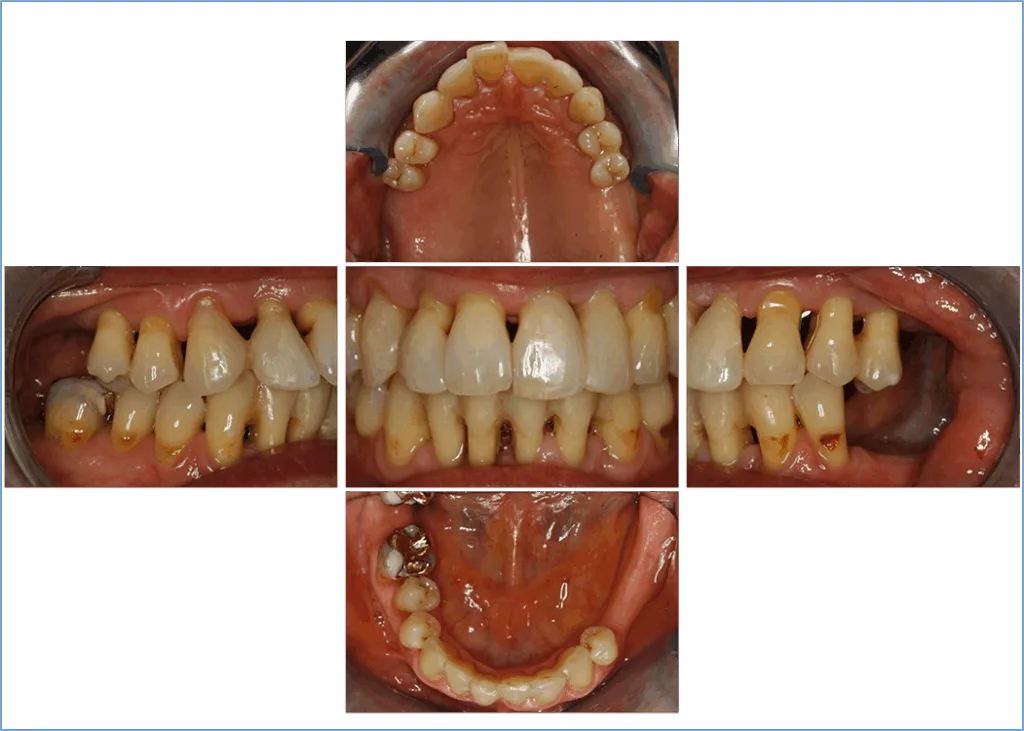

Bei unauffälliger Allgemeinanamnese ohne bekannte Medikamentenunverträglichkeiten oder Allergien und als Nichtraucherin schien das allgemeinmedizinische Risikoprofil erst einmal gering. Hier fiel lediglich der permanent hohe Stresslevel – selbstberichtet durchschnittlich 8-9/10 – auf. Im klinischen Befund (Abb. 3) zeigte sich eine Restdentition mit 11 fehlenden Zähnen (18–16, 26–28, 35–38 und 48), deutlichen Gingivaretraktionen und einer Auffächerung der oberen Frontzähne aufgrund der Überbelastung bei beidseitigem Stützzonenverlust. Abgesehen von den Zähnen 12 und 41 imponierte der marginale Gingivarand entzündungsfrei (Abb. 3). Bei den erhobenen Sondierungstiefen lagen 40% der Messstellen bei Werten ≥ 4 mm und 6% ≥ 6 mm (Abb. 4). Die maximalen Sondierungstiefen mit Werten von 6 bis 7 mm fanden sich an den Zähnen 12 (v), 23 (m-b), 43 (m-li), 41 (m-v, m-li), 43 (m-v, m-li). Eine Furkationsbeteiligung war an Zahn 46 mit Grad I von bukkal und Grad II von lingual zu erkennen. An Zahn 12 wurde vestibulär ein klar tastbares Konkrement detektiert, was die deutlich erkennbare entzündliche Gingiva in diesem Bereich erklärt (Abb. 3). Eine Sondierungsblutung trat bei 10% der Messstellen auf.

Derman